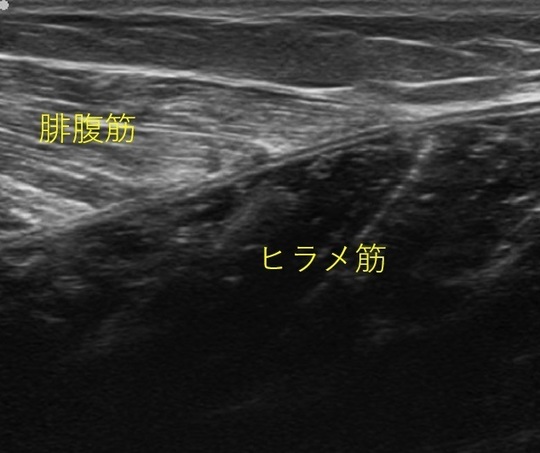

正常なエコー画像(腓腹筋とヒラメ筋)